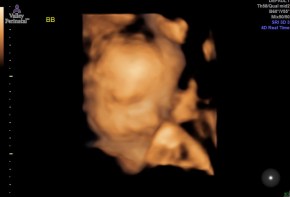

- Baby B’s 3-D Ultrasound

number of appointments or if we want to stay on the current appointment schedule. We will discuss our options with the doctor when we see them next Tuesday. We got a lot of really good pictures of Baby A at the ultrasound, and while Baby B let the tech get some pictures she wasn’t as cooperative as A.